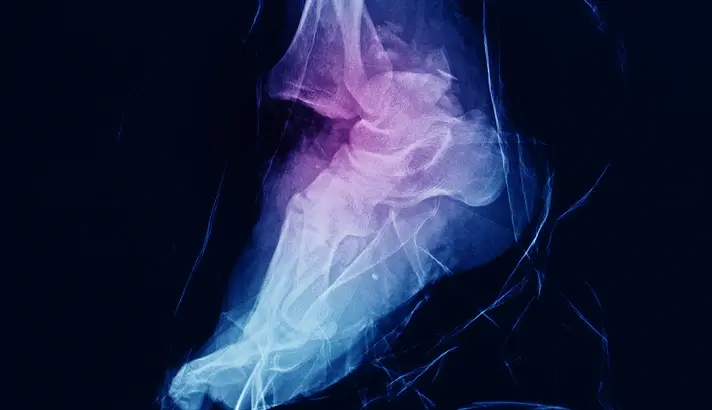

CT and MRI Scans

For more complex fractures, especially those involving the joint surface, a CT scan may be recommended. CT imaging provides a detailed three-dimensional view of the fracture pattern, which is helpful for surgical planning. An MRI scan is not routinely required for most ankle fractures but may be used if a stress fracture is suspected despite normal X-rays, or if there is concern about significant cartilage, ligament or tendon injury.